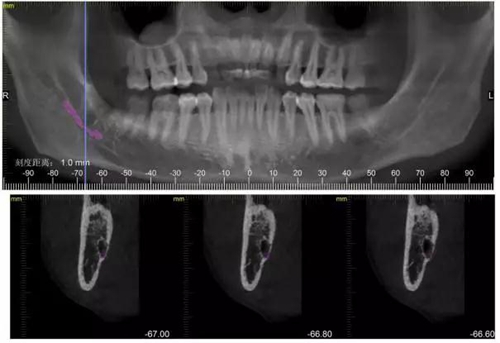

下面CBCT,可以看到兩個牙根的根尖三分之一在神經(jīng)管里面。

CBCT神經(jīng)管標(biāo)線,可以看到標(biāo)線不能連續(xù),中間被阻斷。

下面拔除后的片子,可以清楚的看到,牙根穿破神經(jīng)管。